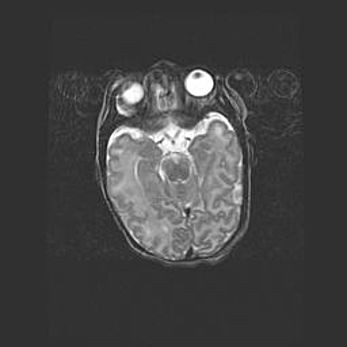

Мальформация Денди-Уокера. Киста задней черепной ямки.

Агенезия мозолистого тела.

Возраст: 2,5 месяца

Вес: 2420 г

Пол: женский

Окружность головы: 37 см

Срок гестации: 32 недели

Мальформация Денди—Уокера — редкий вид патологии ЦНС, представляющий собой врожденный порок развития каудального отдела ствола и червя мозжечка, ведущий к неполному раскрытию срединной (Мажанди) и латеральных (Лушка) апертур IV желудочка мозга. Для этогно синдрома характерна триада симптомов: гипотрофия червя мозжечка и/или полушарий мозжечка, кисты задней черепной ямки, гидроцефалия различной степени. В 70% случаев порок сочетается и с другими аномалиями головного мозга, в частности с агенезией мозолистого тела.